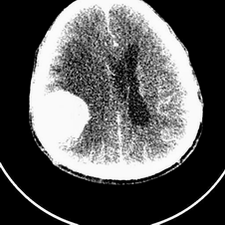

标题: CT25808:男,48岁,头痛多年,近段时间头痛加重伴步态不稳 [打印本页]

标题: CT25808:男,48岁,头痛多年,近段时间头痛加重伴步态不稳

平扫:右颞顶叶病灶呈等低密度伴大面积水肿,脑室受压变形。增强:病灶显著强化。考虑淋巴瘤或黑色素瘤。

1)不排除黑色素瘤可能;建议行mri检查。2)大脑镰下疝。3)脑积水(梗阻性)。